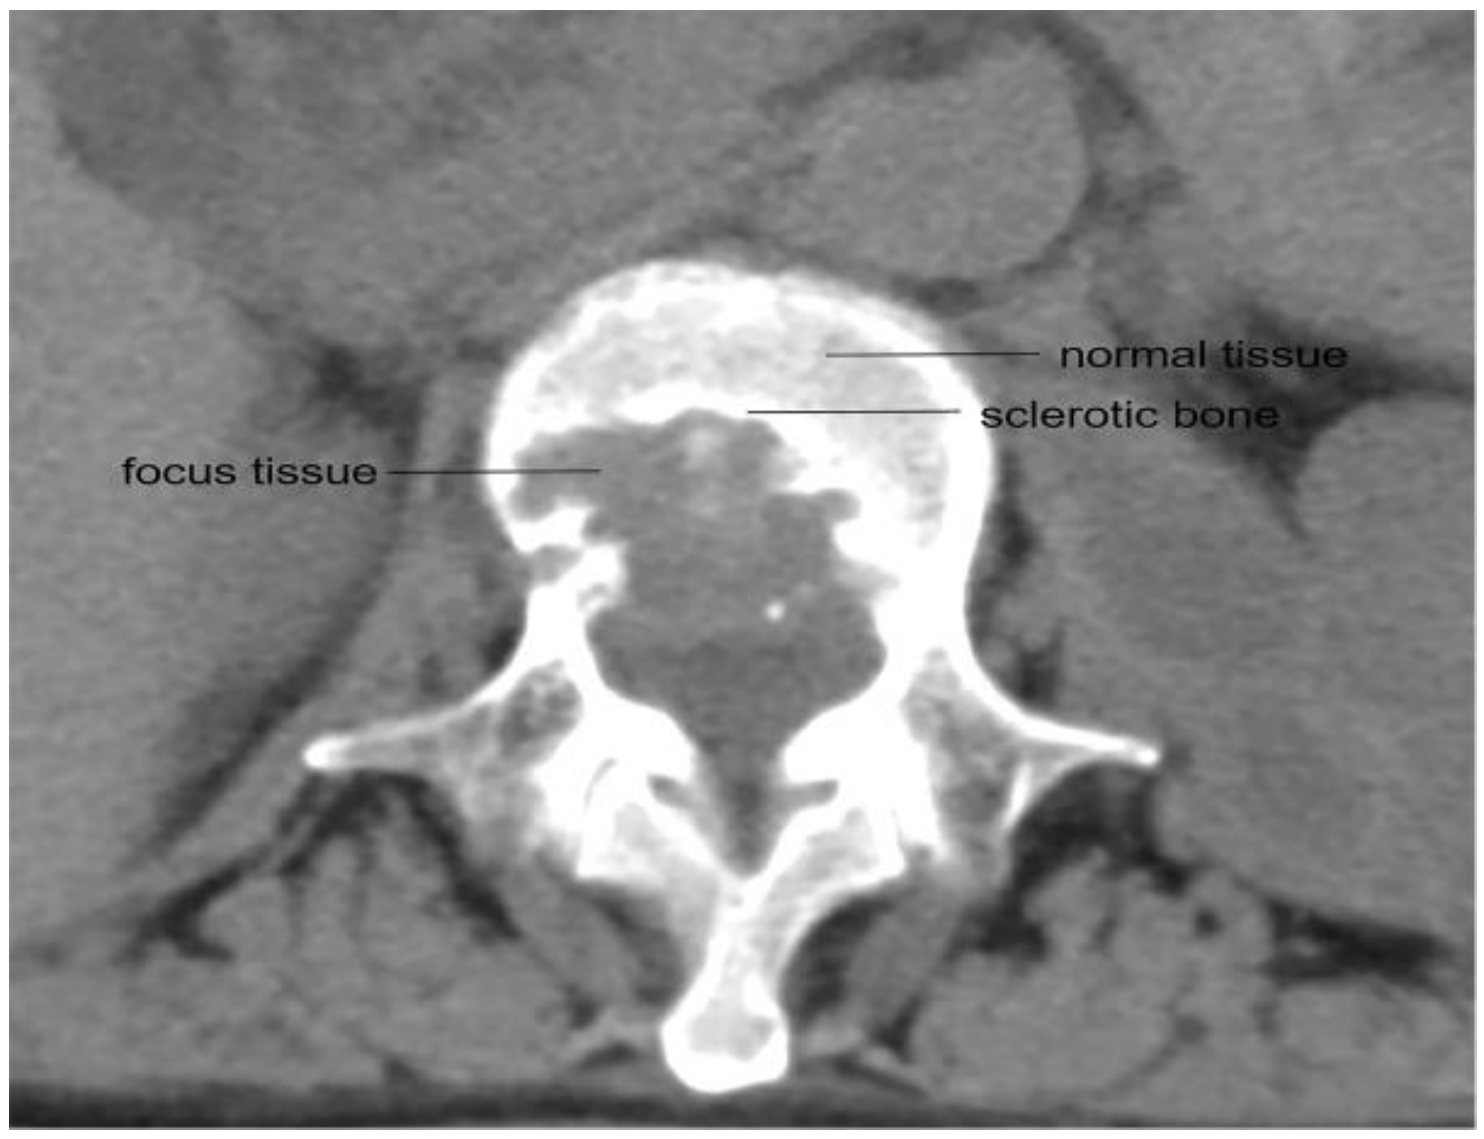

3.1. Patient Characteristics